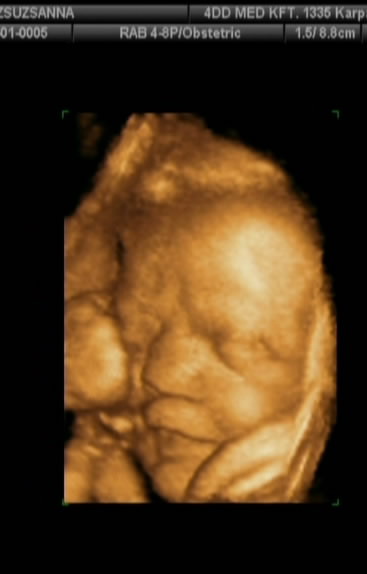

Voltunk kedden 4d-s uh,össze-vissza adatokat mért a gép.

2023g baba súlya, ami 31 hetesnek,

feje 30hétnek , combcsontja 31,pocak 35,végül kidobta,hogy 32 hetesnek felel meg a méretei alapján baba.

3 kilonál ne számítsak nagyobb babára azt mondta a dokinéni,de az én méreteimhez ez is bőven elég lesz.